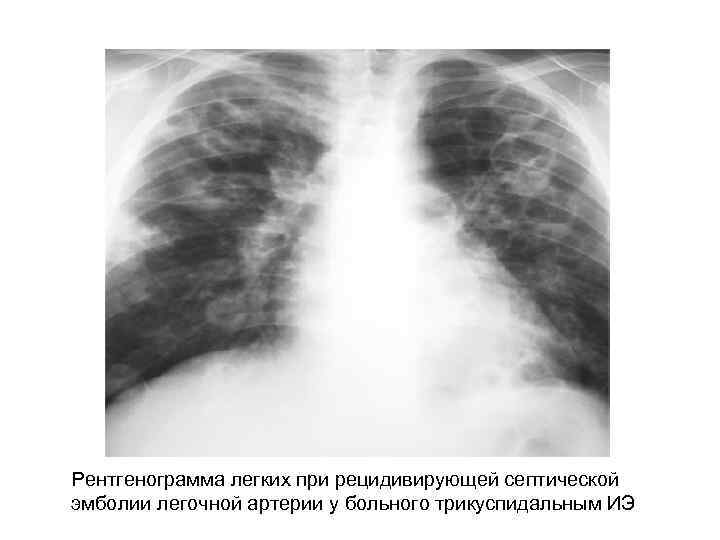

Поражение легких при ИЭ трикуспидального клапана у наркоманов • Синдром септической эмболии легочной артерии 90, 9% (65 -100%) • Синдром острого повреждения легких, острый респираторный дистресс-синдром 12, 5% (13, 2% ) • Пневмония, вызванная Pneumocystis carinii у наркоманов больных СПИД В. И. Уланова, В. И. Мазуров 2007

Осложнения септической эмболии легочной артерии при ИЭ правых отделов сердца • Инфильтративные изменения в легких выявляются рентгенологически у 83 %¹ (55100%)² • 1 по нашим наблюдениям • 2 по данным литературы (В. И. Уланова, В. И. . Мазуров 2007; Zuo L, Guo S, Rong F 2001; Karchmer A. W. 2005; Zuo LE, Guo S. 2007; Moss R, Munt B. 2003; Remetz MS, Quagliarello V 1992; Robbins MJ, Soeiro R, Frishman WH et al. 1986. ) • Абсцесс легких; • Плевральный выпот; • Эмпиема плевры; • Инфаркт легких; • Легочное кровотечение; • Пневмоторакс; • Микотическая аневризма легочной артерии

Рентгенологические признаки СЭЛА при ИЭ • двустороннее поражение; • наличие множественных небольших, нечетких округлых или овальных теней различных размеров (у 68% ), очаговых инфильтратов (у 54%) и клиновидных теней (у 22%) расположенных чаще всего в периферических зонах легких или субплеврально; • склонность к распаду инфильтратов с возникновением абсцессоподобных полостей (у 50%) и кист (у 81%); • быстрая динамика появления новых инфильтратов и медленное обратное развитие с длительным сохранением кистовидных тонкостенных полостей; • возможно развитие плеврального выпота (у 50%) и редко пиопневмоторакса. По данным Zuo LE, Guo S. (2007)

Рентгенограмма легких при рецидивирующей септической эмболии легочной артерии у больного трикуспидальным ИЭ

Руководство по ИЭ Европейского общества кардиологов 2004: Множественные быстро меняющиеся легочные инфильтраты вызывают подозрение на ИЭ правых отделов сердца